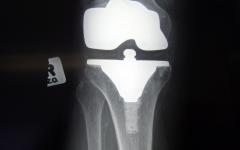

Ранното прохождане уврежда коленете

Една от най-честите причини за посещение при личния лекар е болката в коленете, особено силна при клякане и при слизане по стълби. Това често се съпровожда със ставни изливи, така наречената „вода в коляното“.